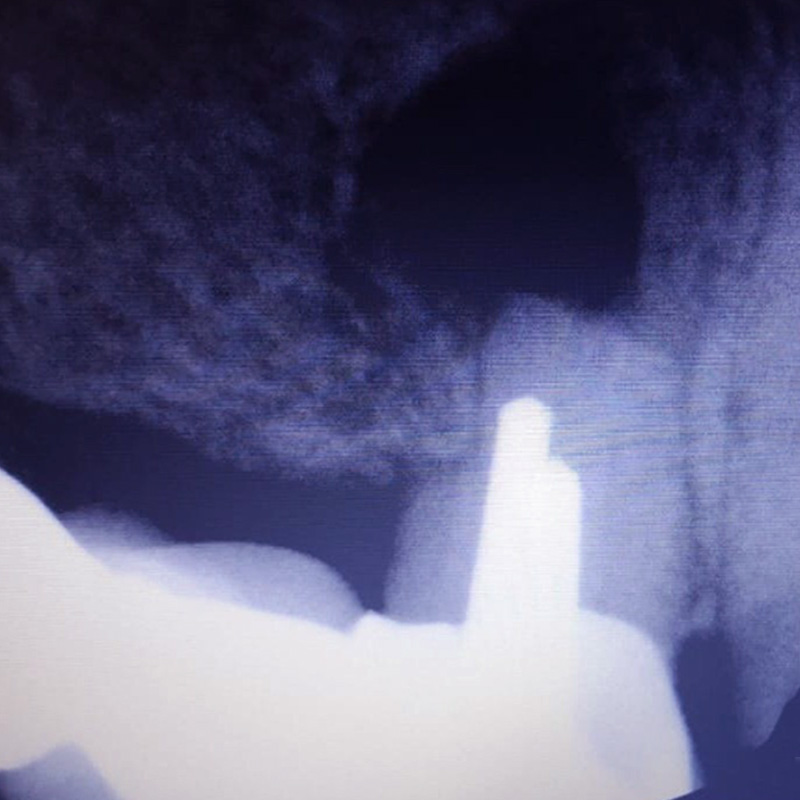

В нашу клинику обратился пациент с жалобами на резкую боль при накусывании справа вверху в области мостовидного протеза, который был установлен в другом лечебном учреждении.

После анализа сделанной рентгенограммы, врач-хирург Тарасов Денис Геннадьевич провёл резекцию верхушки корня зуба 1.4.

При неэффективности терапевтического лечения путём резекции верхушки корня одновременно с частью корня отсекается очаг воспаления в канале.